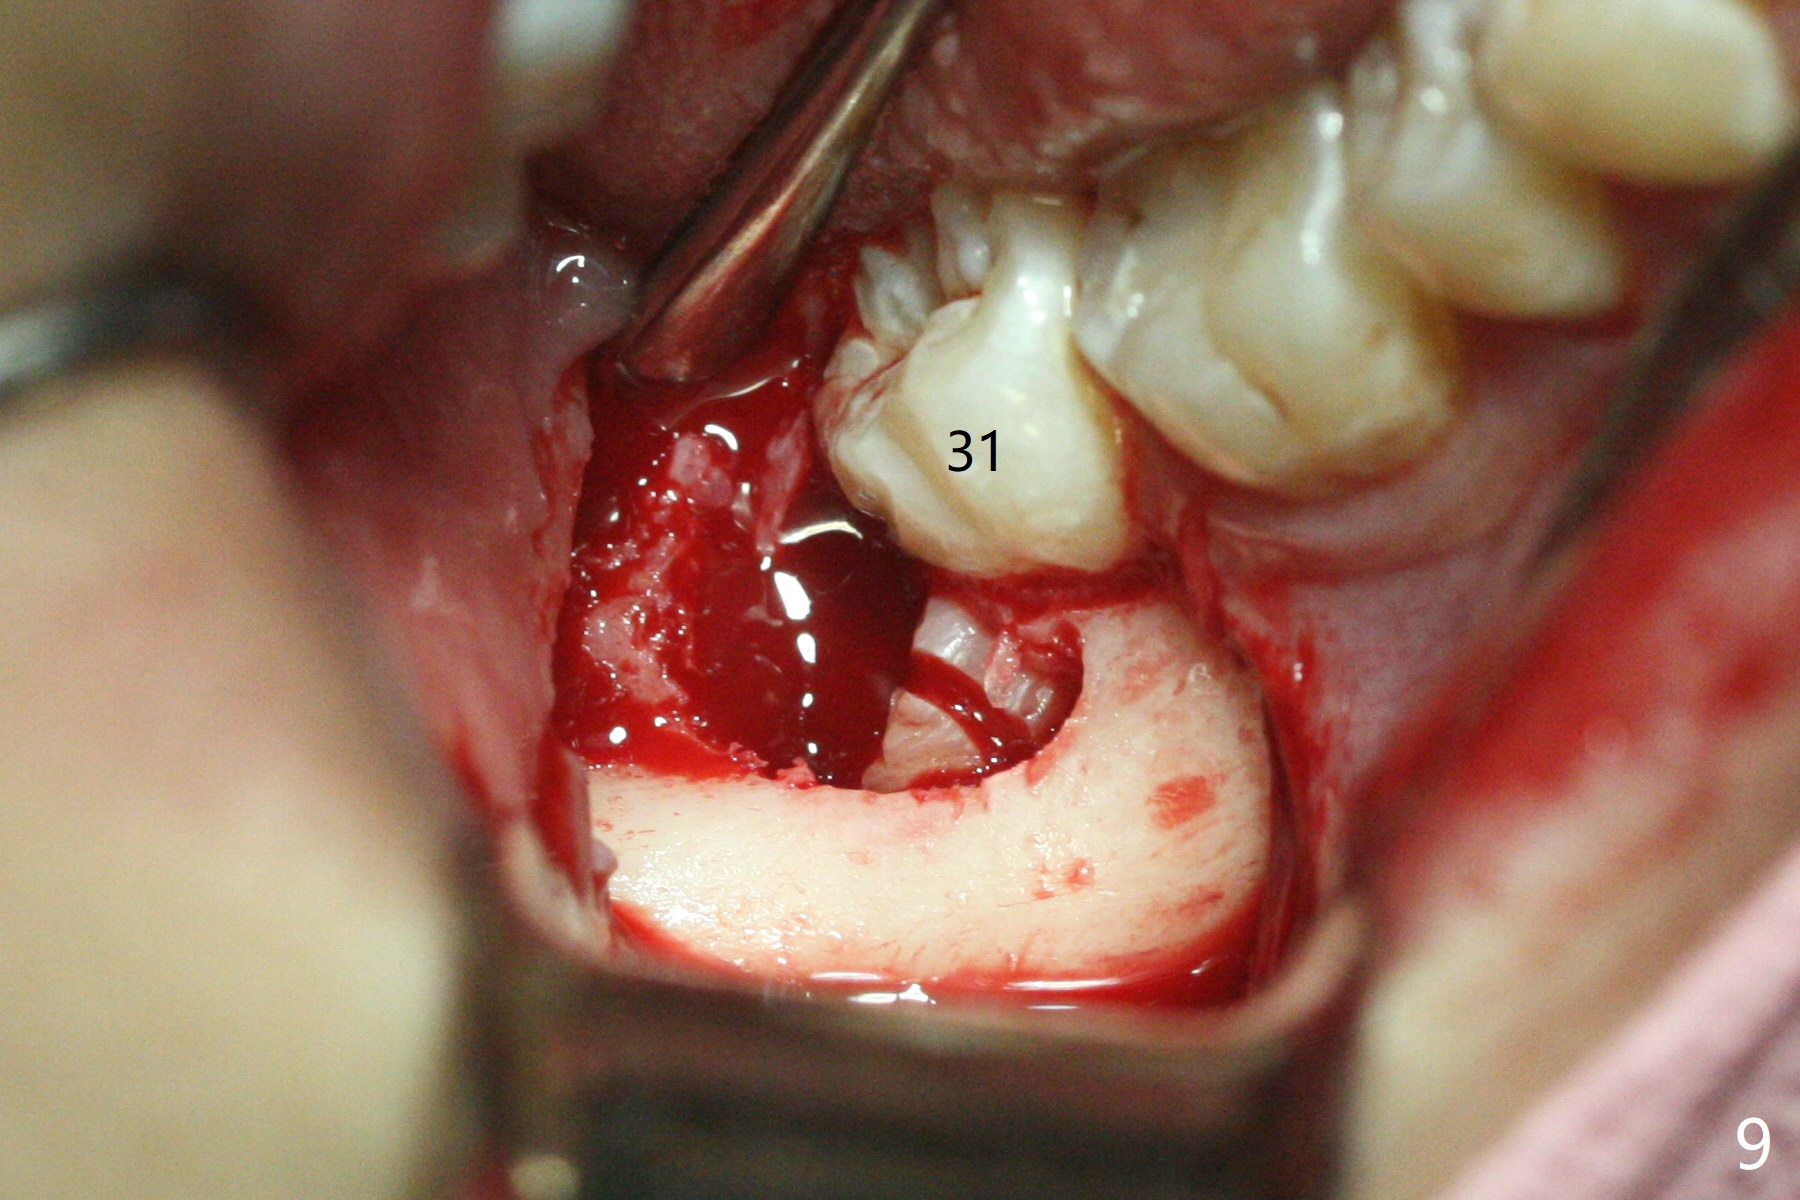

左下,右下智齿(图九)的确位于第二磨牙颊侧,事先附加切口近中,缝合后伤口不易裂开,骨粉丢失。